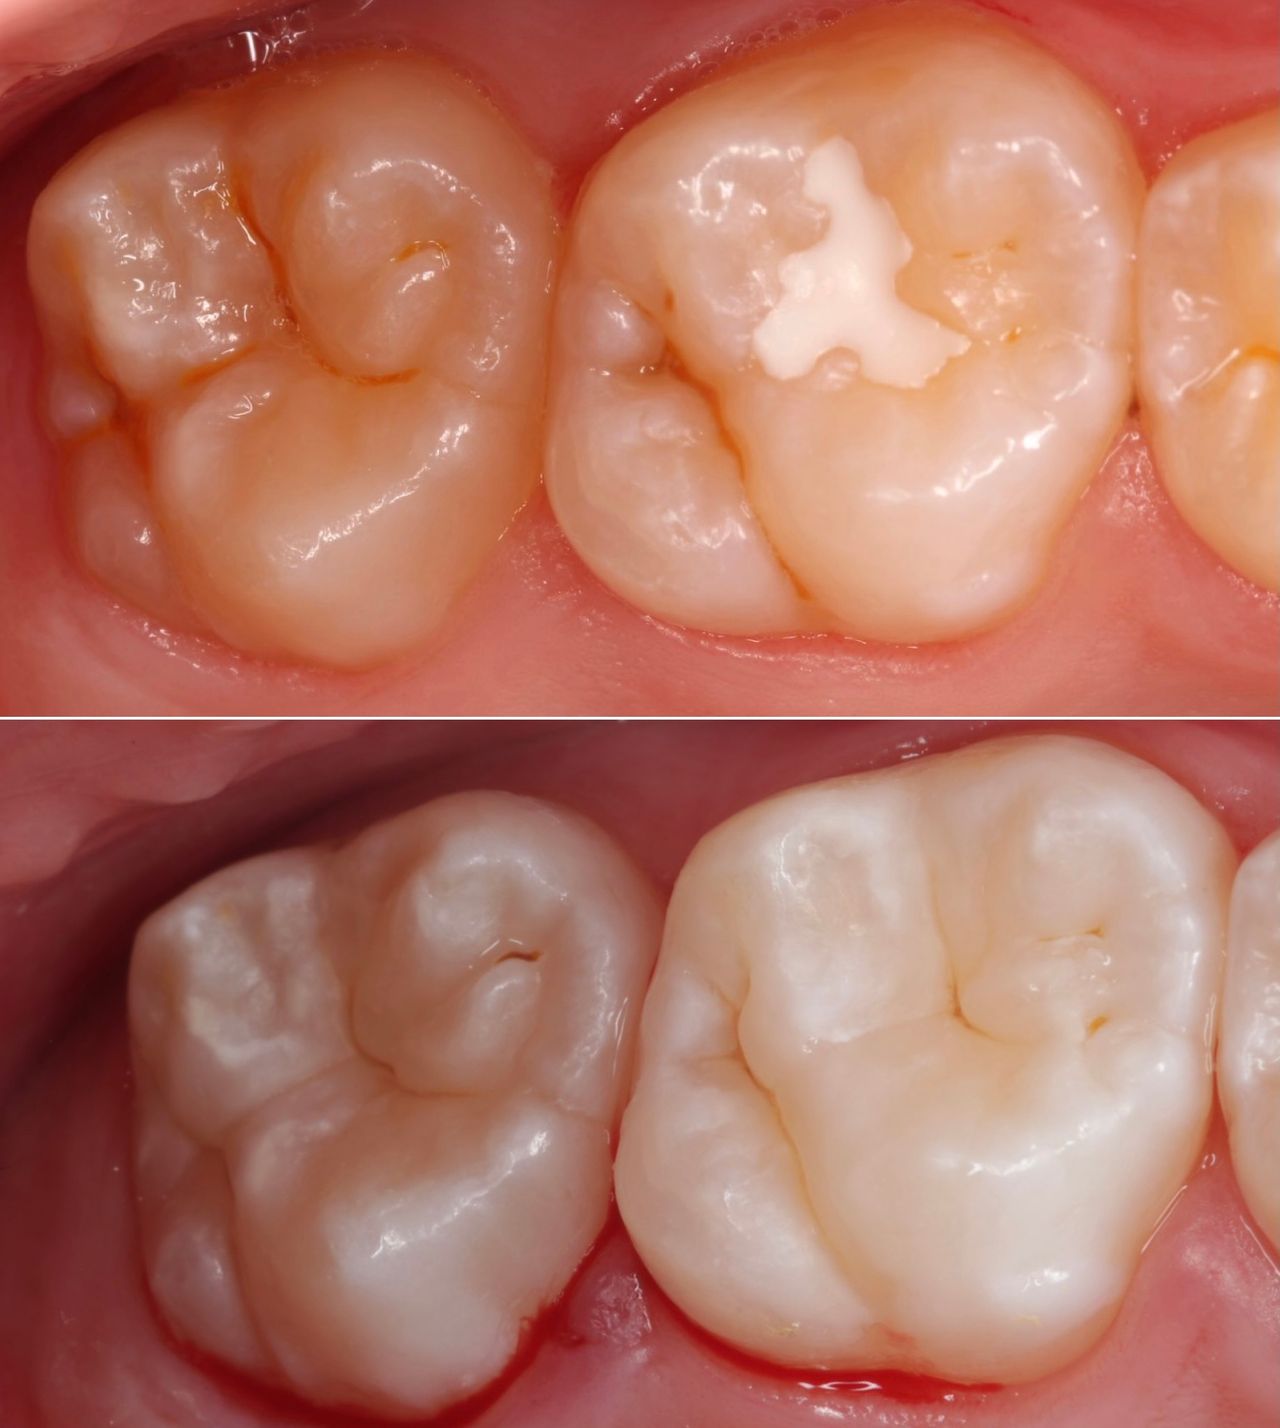

Jej pasją jest leczenie zachowawcze, wypełnienia z jej ręki są małymi dziełami sztuki, idealnie i anatomicznie wykończonymi. Precyzja i cierpliwość w sposobie pracy w połączeniu z wysokim poczuciem estetyki umożliwiły tej naturalny rozwój w kierunku stomatologii estetycznej. Dr Valeriia wykonuje precyzyjne kompozytowe odbudowy zębów przednich, bondingi oraz prace „z ręki”.

Doktor uważa, że obraz mówi więcej niż słowa, zapraszamy do zapoznania się z galerią jej prac.